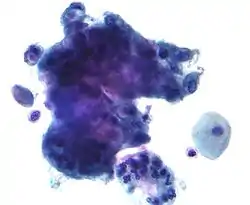

Endocervical adenocarcinoma on a pap test.

Endocervical adenocarcinoma on a pap test. Candida organisms on a pap test.